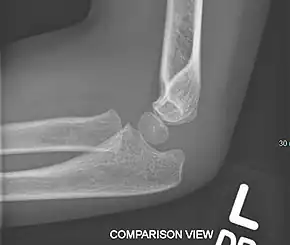

Elbow fracture

Elbow fractures are any broken bone in or near the elbow joint and include olecranon fractures, supracondylar humerus fractures and radial head fractures.[1]

The terrible triad of the elbow (not to be confused with the terrible triad of the knee) is a combination of:[2]

- A fracture of the head of radius

- A fracture of the coronoid process of the ulna

- Humeroulnar dislocation (generally posterior or posterolateral)

The terrible triad of the elbow is confers joint instability and a major risk of developing osteoarthritis.[2]